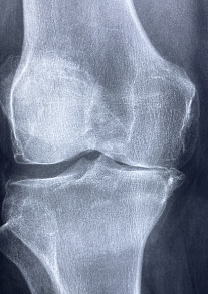

무릎 관절 통증 증상

무릎 관절 통증의 증상은 다음과 같습니다.

- 통증: 무릎 관절에서 뚜렷한 통증이 느껴지며, 증상은 경도에서 중등도, 심하게 나뉘어질 수 있습니다. 통증은 특히 무릎을 움직이거나 앉거나 일어설 때 더욱 심해집니다.

- 운동 제한: 무릎 관절의 통증으로 인해 보행, 오르내리기, 앉기, 일어서기 등의 일상적인 운동이 제한될 수 있습니다.

- 부종: 무릎 주변에 부종이 발생할 수 있으며, 무릎 관절 주변이 뜨거워지거나 붉어질 수 있습니다.

- 슬관절 혹은 허벅지 근육 경련: 무릎 관절 통증으로 인해 슬관절이나 허벅지 근육에 경련이 발생할 수 있습니다.

- 무릎 관절의 소리: 무릎 관절에서 달리는 소리나 뻑뻑한 소리가 날 수 있습니다.

무릎 관절 통증은 각종 원인에 따라 발생할 수 있으며, 증상의 정도와 진행 정도에 따라 치료 방법이 결정됩니다. 따라서, 증상이 있는 경우에는 전문가의 진단과 치료를 받는 것이 중요합니다.